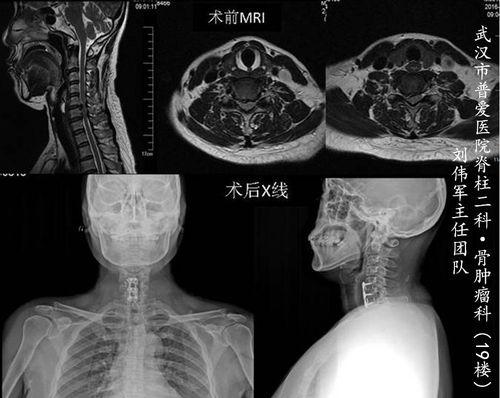

为了让大家更直观地了解颈椎前路手术的过程,我们找到了一段手术视频。下面,就让我们一起走进手术室,见证这一神奇的医疗过程。

手术前,医生会对患者进行详细的检查,确保手术的安全性。同时,患者也会接受一系列的术前准备,如禁食、备皮等。

医生会逐层切开皮肤、肌肉等组织,直到暴露出颈椎。在这个过程中,医生会仔细观察颈椎的情况,确定手术方案。

医生会切除病变的椎间盘、骨刺等组织,以解除对神经根或脊髓的压迫。切除过程中,医生会尽量保留正常的颈椎结构,以减少手术对颈椎的影响。

为了恢复颈椎的稳定性,医生会在切除病变组织后,植入人工椎间盘或椎体。这些植入物可以模拟正常椎间盘的功能,减轻颈椎的压力。